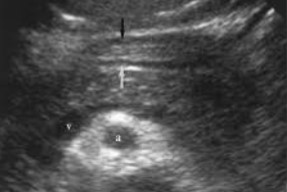

This image was taken in what plane?

Explain your answer.

Transverse

The entire pancreas is visualized